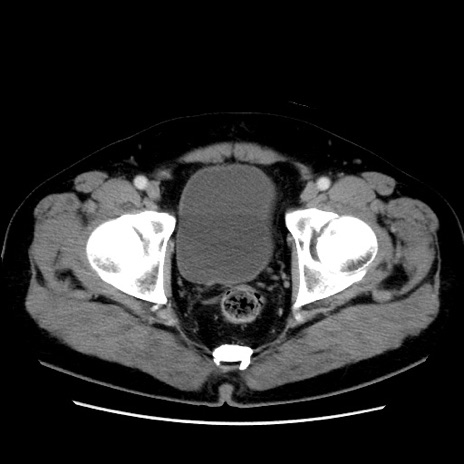

症例16(横断像)

【症例】 70歳代男性

【主訴】 腹痛、嘔吐

【現病歴】 約1ヶ月前より間欠的に腹痛と嘔吐あり、当院消化器内科を受診したところCTで多発する肝臓のLDAを指摘され、精査中であった。以降は消化器症状は安定していたが、2日前より嘔気と腹痛があり、同日より排便・排ガスが消失した。改善認めず、 本日、救急外来を受診した。

【既往歴】 大腸ポリープ切除後。

【身体所見】意識清明・会話良好、BT 36.3℃、BP 127/80mmHg、 P 80bpm、腹部:膨満あり、平坦・軟、上腹部正中および下腹部正中に圧痛あり、反跳痛なし、筋性防御なし。

【データ】WBC 7200、CRP 0.77